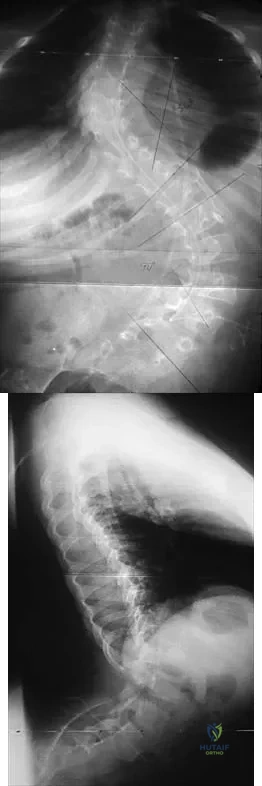

Question 14

The lesion seen in Figure 4 is most likely the result of metastases from what solid organ?

Explanation